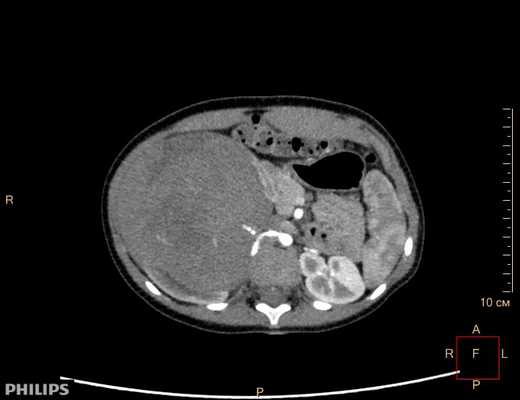

- Компьютерная томография органов брюшной полости и забрюшинного пространства с оральным и внутривенным контрастированием (см. рис. 1).

Рисунок 1. КТ брюшной полости ребенка с большой нефробластомой с метастазами в печень.

Клинически: при пальпации опухоль в проекции правой почки до 12 см в диаметре. Общеклинические исследования в пределах возрастной нормы. При КТ органов брюшной и грудной полости: КТ-картина объемного образования правой почки без признаков интрапульмональных метастазов (см. рис. 2). УЗИ брюшной полости: в проекции правой почки солидно-кистозное образование 101ґ114ґ99 мм, объемом 500 мл, васкуляризация активная, интактная часть почки 57ґ12ґ40 мм. Объемное образование правой почки — опухоль Вильмса. Предварительный диагноз: опухоль Вильмса правой почки, 2-я стадия.

Ребенку проведена предоперационная химиотерапия. На 5-й неделе лечения КТ-контроль показал уменьшение опухоли в размерах до 90ґ80ґ100 мм (см. рис. 3).